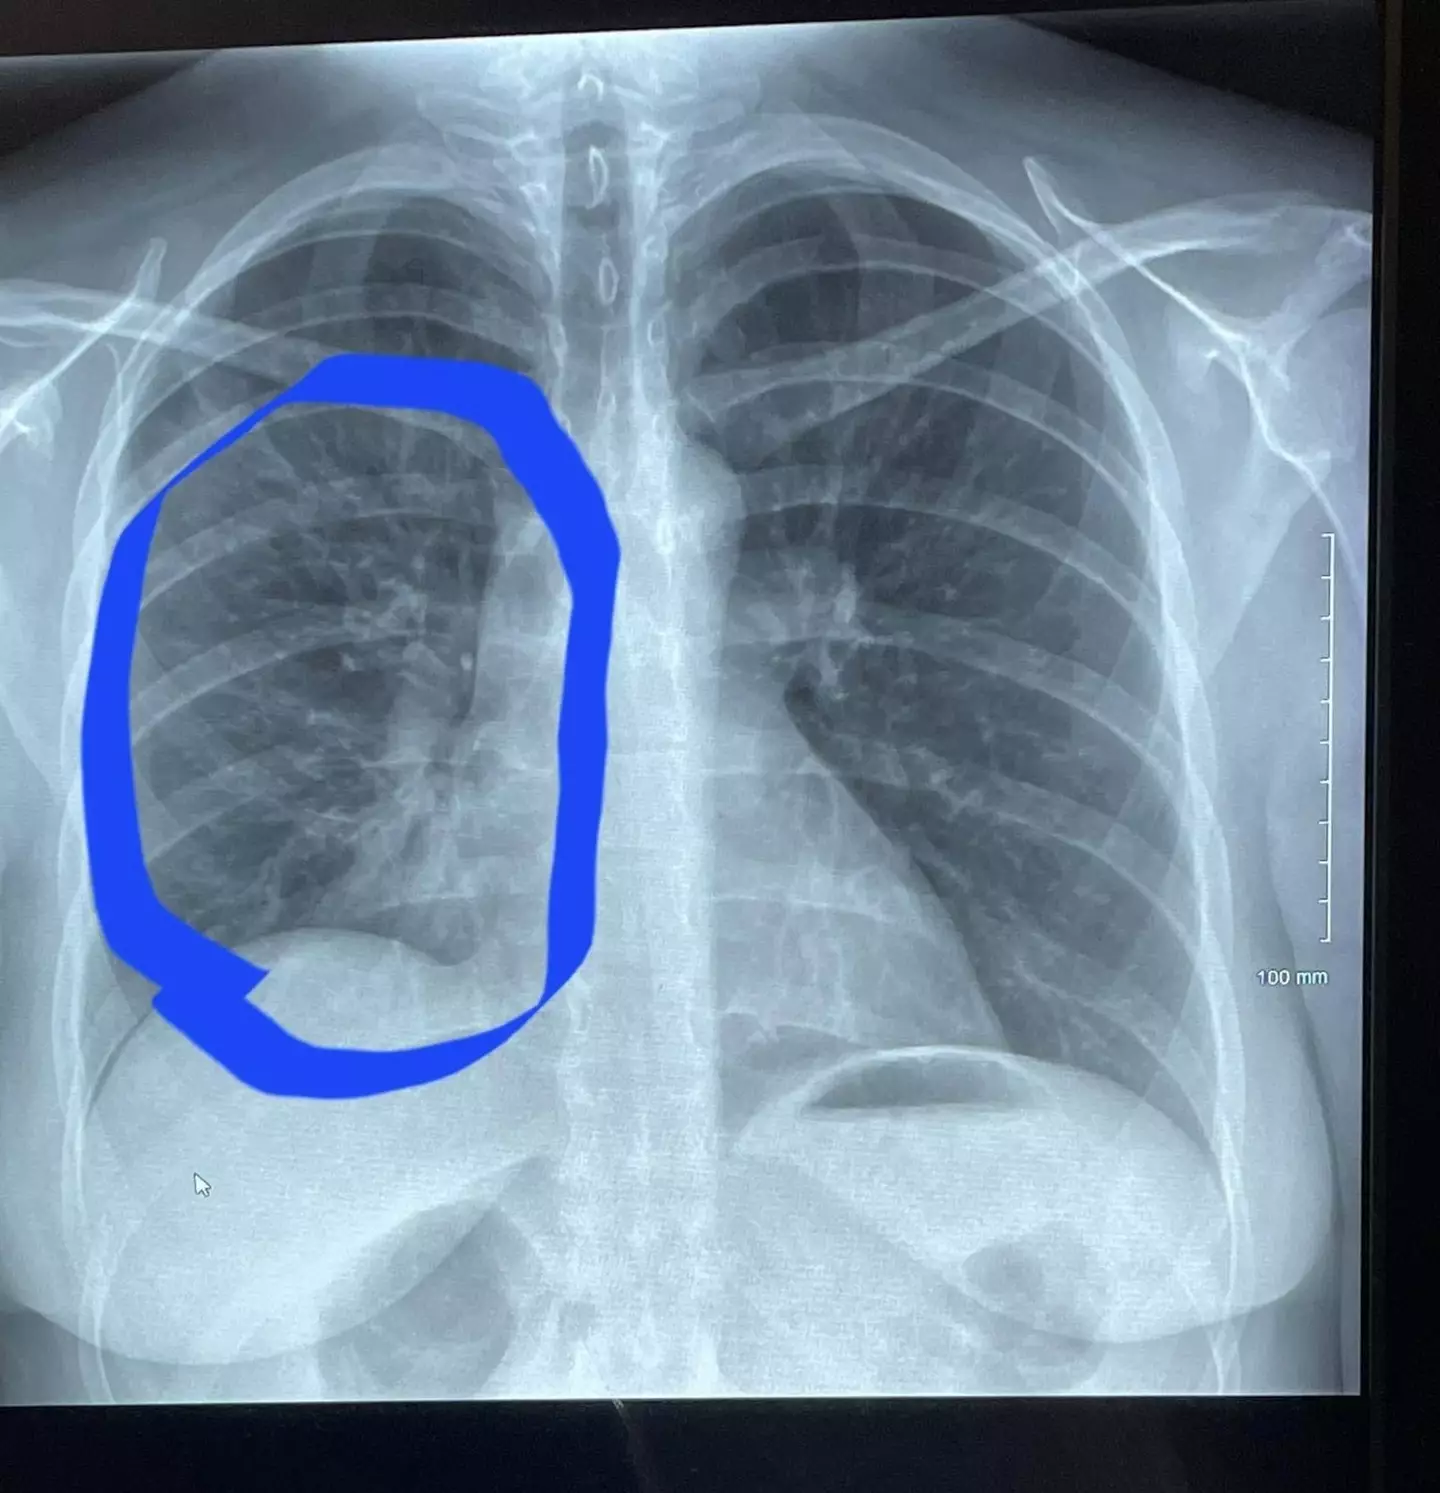

After Roth went back to the hospital's emergency department in Scott County, doctors informed her she had an obstruction in her right lung.

"They said it was pneumonia," she said. "It looks like a tree with branches, it's called 'tree budding' and it's basically the deterioration of your lung.

"It's not supposed to happen unless you're a really heavy smoker."

The doctor showed Roth the scans of her lungs and pointed out they didn't look like they should for a 30-year-old woman, but instead of someone who had been 'a smoker of ten years'.

"I looked like I had the lungs of someone in their 80s, someone much older, when he showed me that first scan.